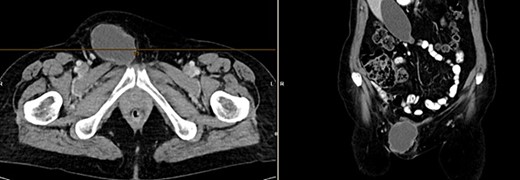

Further clarification was sought through a computed tomography (CT) scan of the entire abdomen (Fig. 1). The CT from 25 February 2022 showed an oval, encapsulated structure in the right groin area, most likely interpreted as a soft tissue hematoma. No active bleeding was observed. An enlarged lymph node was considered as a differential diagnosis. A follow-up CT on 1 August 2022 showed a size-progressive formation within the suspected right inguinal hernia compared with the previous examination in February (Fig. 2). There was no evidence of tumor recurrence or metastasis-suspect lesions intra-abdominally. A previous hysterectomy was also noted.

CT of the abdomen from 1 August 2022: size-progressive formation within the right inguinal hernia compared with the previous examination from 25 February 2022; no indication of tumor recurrence or metastasis-suspect lesions intra-abdominally, post-hysterectomy.